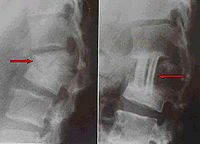

图片说明:左图为治疗前二维CT,右图为微创治疗后3年半

Bkm5m.jpg

Bkm5n.jpg

随访二维CT照片。